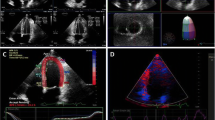

3D Echocardiography (3DE)

3DE (Fig. 4) adds reliability of volumetric assessment by acquiring pyramidal-shaped volumes which avoid the volumetric assumptions and foreshortening that are inherent to conventional 2D echocardiography [21]. Reliability and reproducibility of LVEF and LV volume assessment is increased with 3D imaging [22, 23]. 3DE is a sensitive modality for monitoring long term survivors of anthracycline and radiation exposure [24]. Operator dependence and adequate endocardial detection are major limitations of 3DE. Nevertheless, assessment of LVEF with 3DE is comparable to cardiac magnetic resonance imaging (CMR) and, based on the 2014 joint statement by the ASE and the European Association of Cardiovascular Imaging, is the preferred technique for monitoring LV function in patients with cancer [7••].

Myocardial strain, a physical deformation property of the myocardium, can be assessed using speckle-tracking echocardiography (STE) which tracks natural acoustic reflectors within the myocardium, also known as “speckles”, from frame to frame to determine deformation (strain) and the speed of deformation (strain rate) (Fig. 5). STE has the ability to detect chemotherapy-induced cardiotoxicity through early detection in subtle decreases in ventricular function. Of particular importance, speckle tracking shows cardiotoxic effect of cancer therapy at doses much lower than were previously thought.

Speckle tracking echocardiography illustrating global longitudinal strain in apical four-chamber view (a), apical three-chamber view (b), apical two-chamber view (c), and polar plot (d) in a patient with a normal left ventricular systolic function with a global longitudinal strain of -21.1 % pre-chemotherapy/radiation